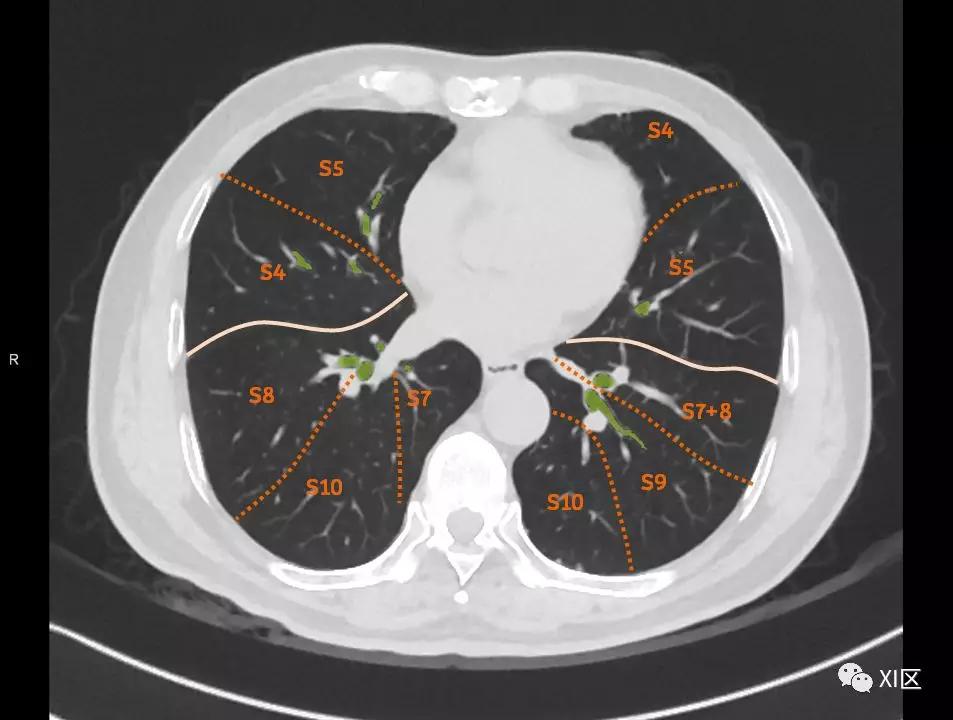

肺的断层分段示意图

在进行肺的分段时,可以上下观察浏览,沿着相应气管的走形可以更容易准确地进行分段。